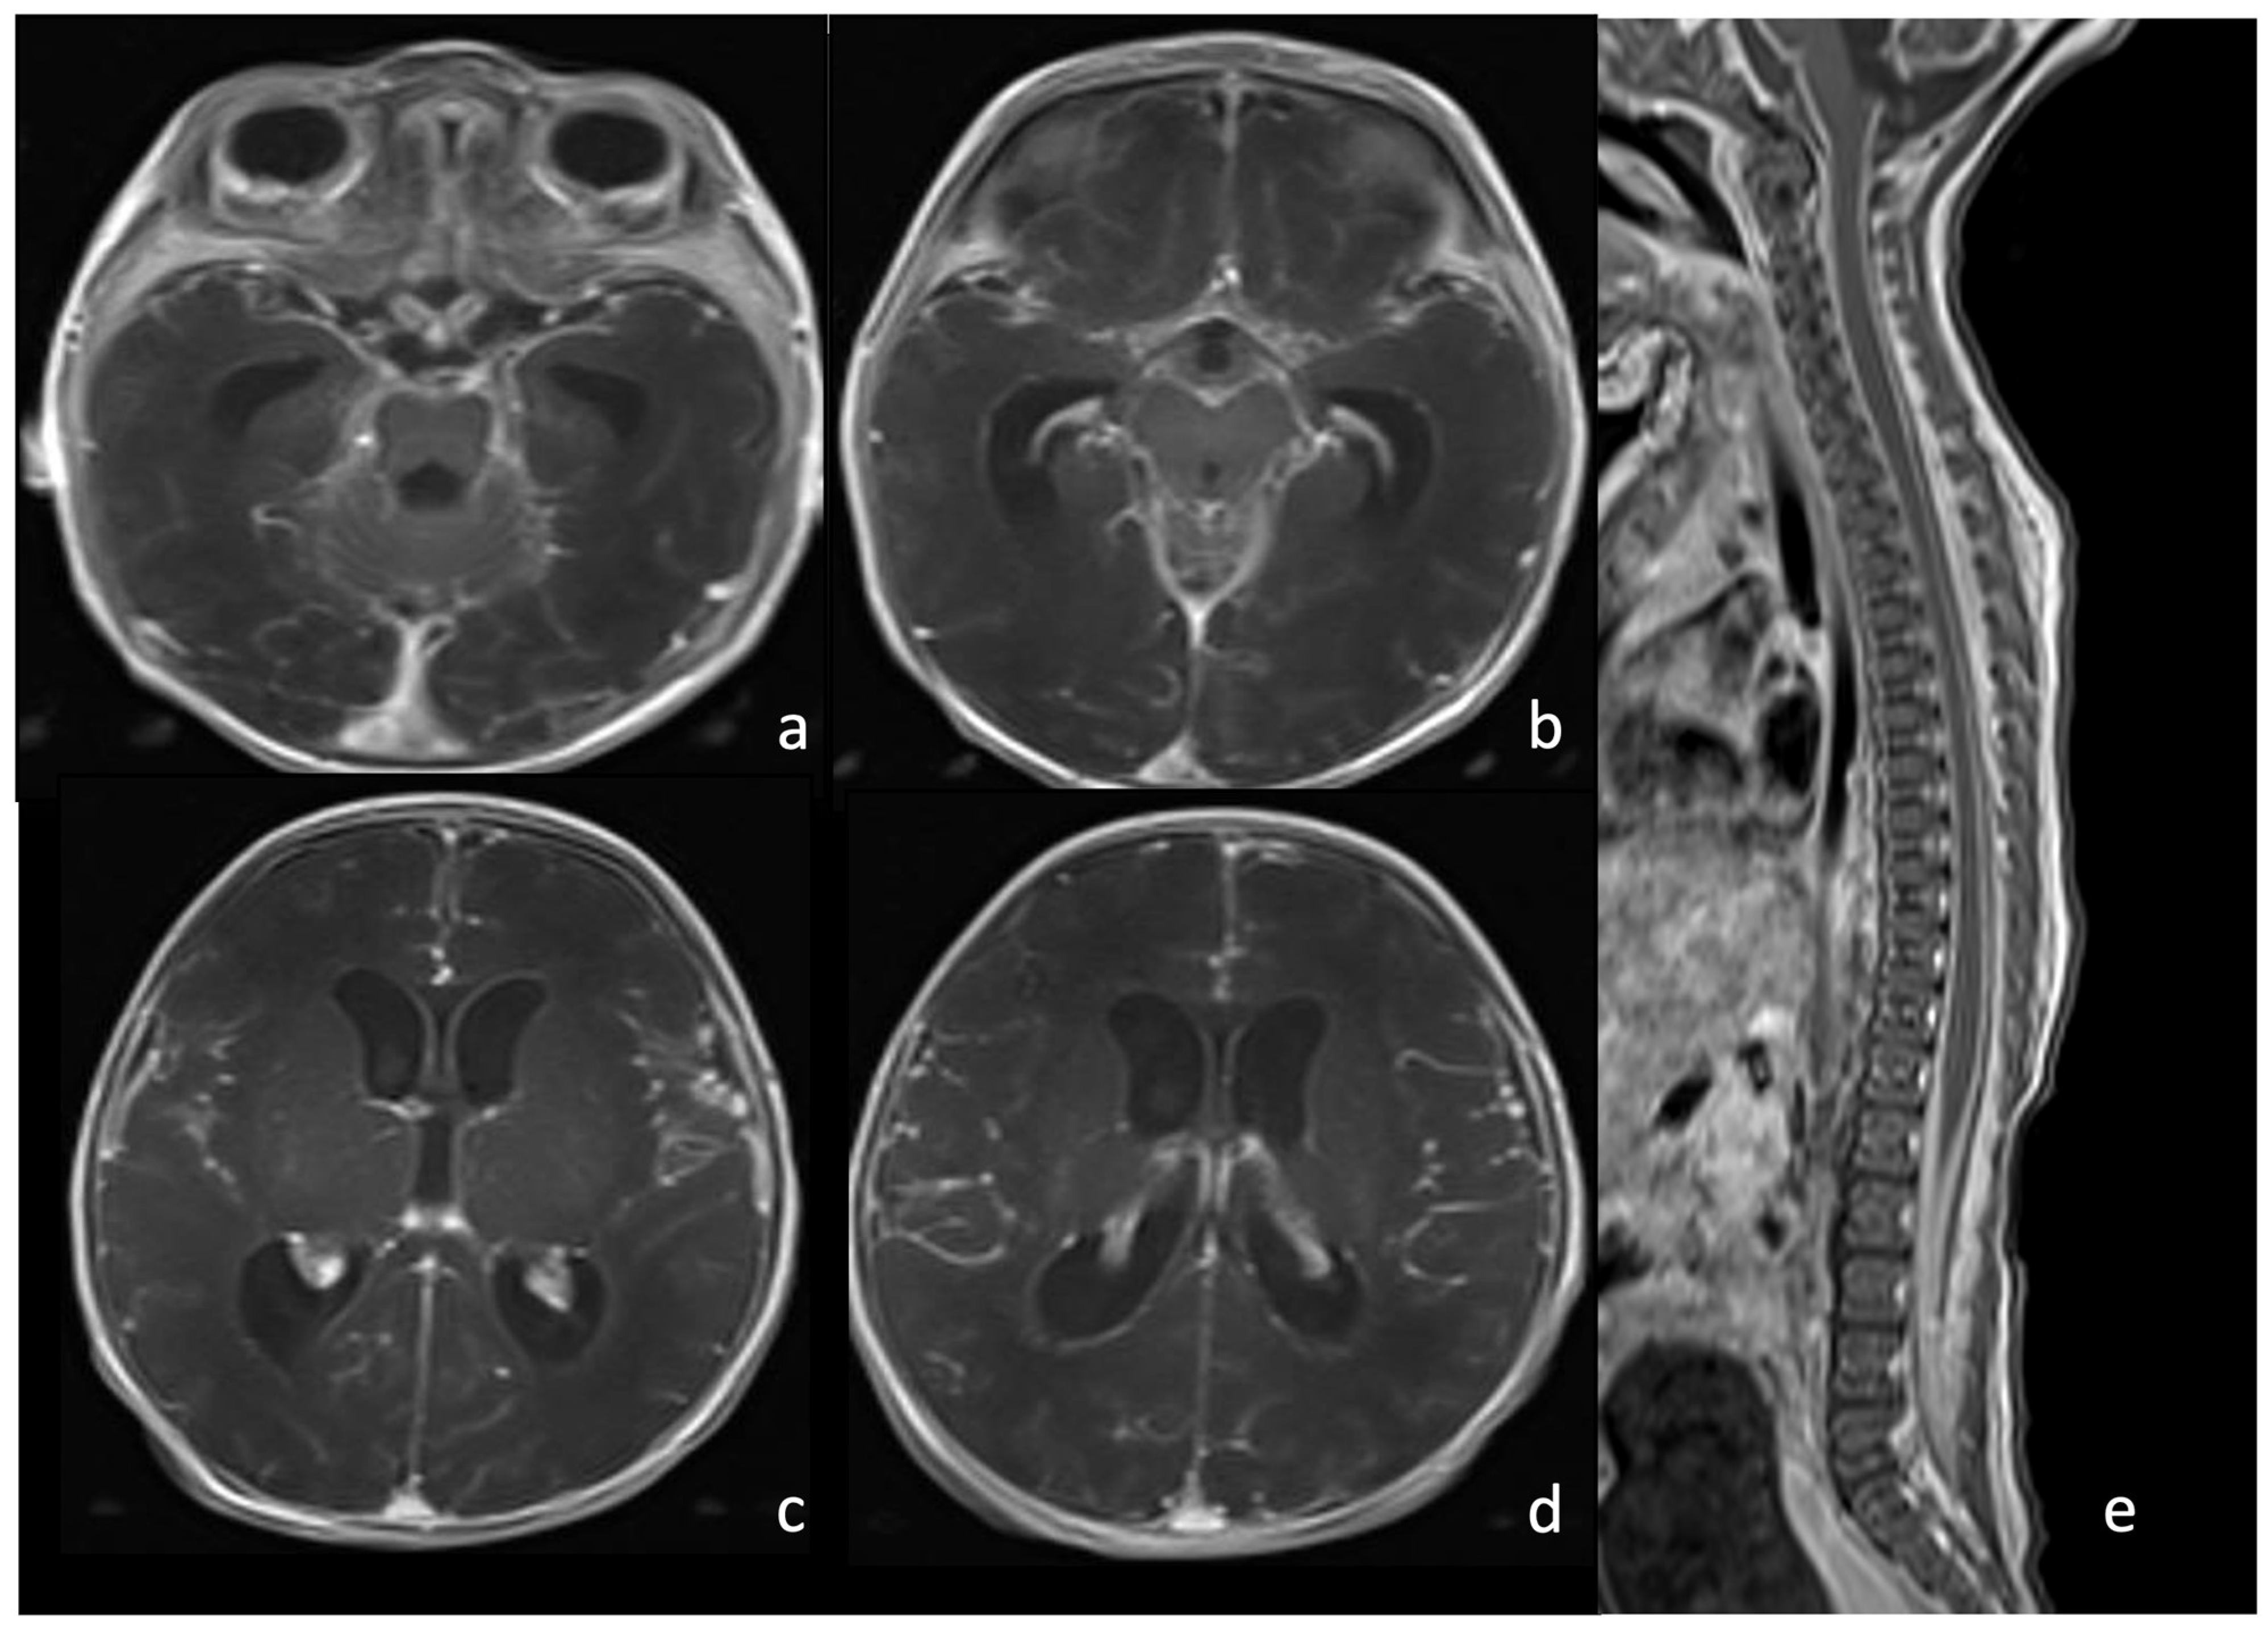

Figure 3.

A 9-day-old boy affected by meningitis caused by Listeria Monocytogenes with ventriculitis. There are hypointense in T2 (arrow in (a), axial T2WI) and hyperintense detritus in T1 (arrow in (b), axial T1-weighted images); a slight contrast enhancement of ventricle wall is visible in (d), axial post- contrast T1 WI, especially if compared with (c) axial pre-contrast T1 WI. There is also a ventriculomegaly visible on both MRI ((e), coronal T2WI; (f), sagittal T1 WI) and US ((g), coronal plane and (h), parasagittal plane). In (f,h), there are also visible hyperintense ((f), arrow) and hyperechogenic detritus ((h), arrow).